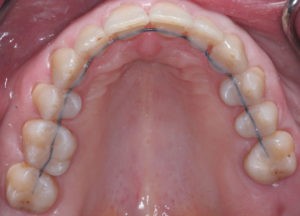

Искривление окклюзионной кривой (плоскости смыкания зубов), возникшее в результате парадонтита, успешно удалось устранить, используя накусочные брекеты на верхних резцах и микроимплант, установленный во фронтальном участке нижней челюсти:

Все этапы ортодонтического лечения и выбор аппаратуры для его осуществления (вид брекет-системы, дополнительные приспособления) согласованы с пациентом.